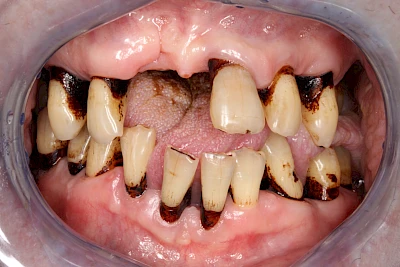

Von außen (exogen) eher dunkel gefärbt und meist mehrere Zähne betroffen:

- Genußmittel (Tee, Kaffee, Rauchen)

- Medikamente (z. B. Eisen)

Bräunliche Verfärbung

Äußere Verfärbungen durch Genußmittel oder Medikamente (Eisen!) lassen sich meist nur durch den Zahnarzt z. B. mit einer professionellen Zahnreinigung entfernen.